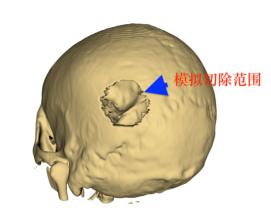

三维重建可见明显颅骨破坏区域

神经重症监护室在肖三潮主任医师指导下,全方位分析患者病情,利用在医学影像数据化处理方面的技术优势,为患者制定了个体化手术方案:术前模拟切除受侵犯颅骨。

同时,根据模拟颅骨缺损范围,设计并制作3D打印模型,运用3D打印支架精确定位肿瘤部位及手术切口。